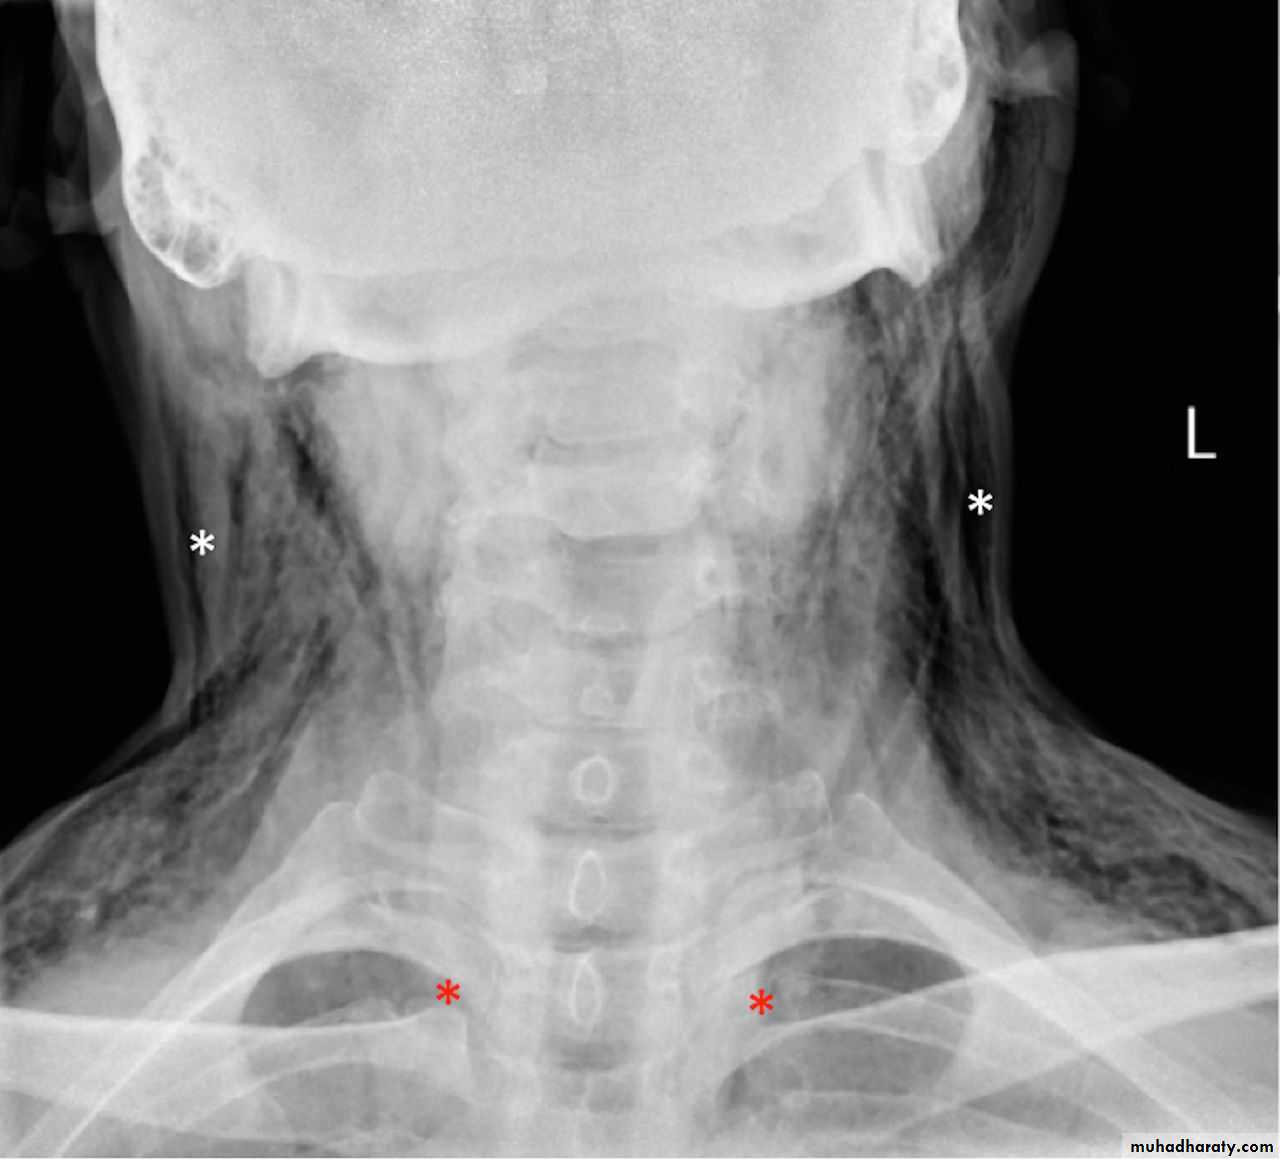

What is a surgical or subcutaneous emphysema?

Surgical emphysema

What is the difference??Surgical Emphysema